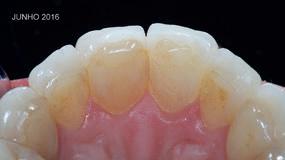

MARÇO 2011 MARÇO 2017

Os tecidos periodontais permaneceram saudáveis (ver Fig. 5) ao longo destes anos, talvez até mais saudáveis do que se a paciente tivesse permanecido com o seu esmalte original, já que a cerâmica feldspática retém menos placa bacteriana que o próprio esmalte2,10. Contribui também para esta sanidade gengival, o facto de a adaptação marginal de uma faceta feldspática ser melhor do que a de outros tipos de restaurações indiretas nomeadamente nas coroas tradicionais cimentadas (em vez de aderidas)11. Com a técnica do modelo refratário utilizada nestas facetas, consegue-se um “gap” de apenas 40 micra11. Além disso, estas restaurações são aderidas ao dente segundo o protocolo recomendado por Pascal Magne, que utiliza compósito micro-híbrido fotopolimerizável aquecido em conjunto com adesivo com carga (Optibond FL), em vez de usar cimentos resinosos, o que proporciona a preservação da qualidade na transição dente-restauração ao longo do tempo, quer a nível estético, quer a nível de rugosidade e de menor desgaste da superfície desse material que preenche o referido “gap”4 .